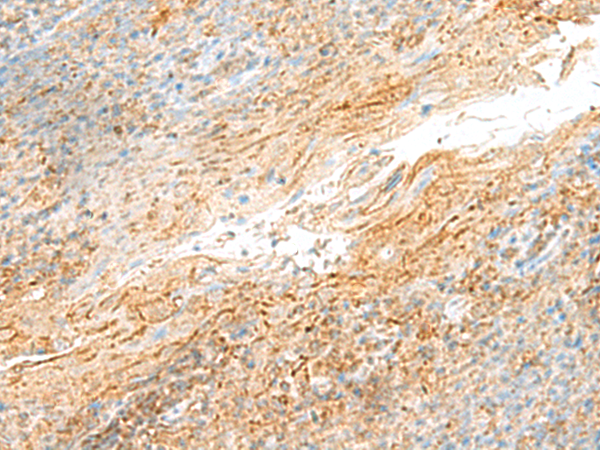

分类: 科研抗体货号: P09884别名: DR4; DRB4; HLA-DR4B应用: WB,IHC反应种属: Human